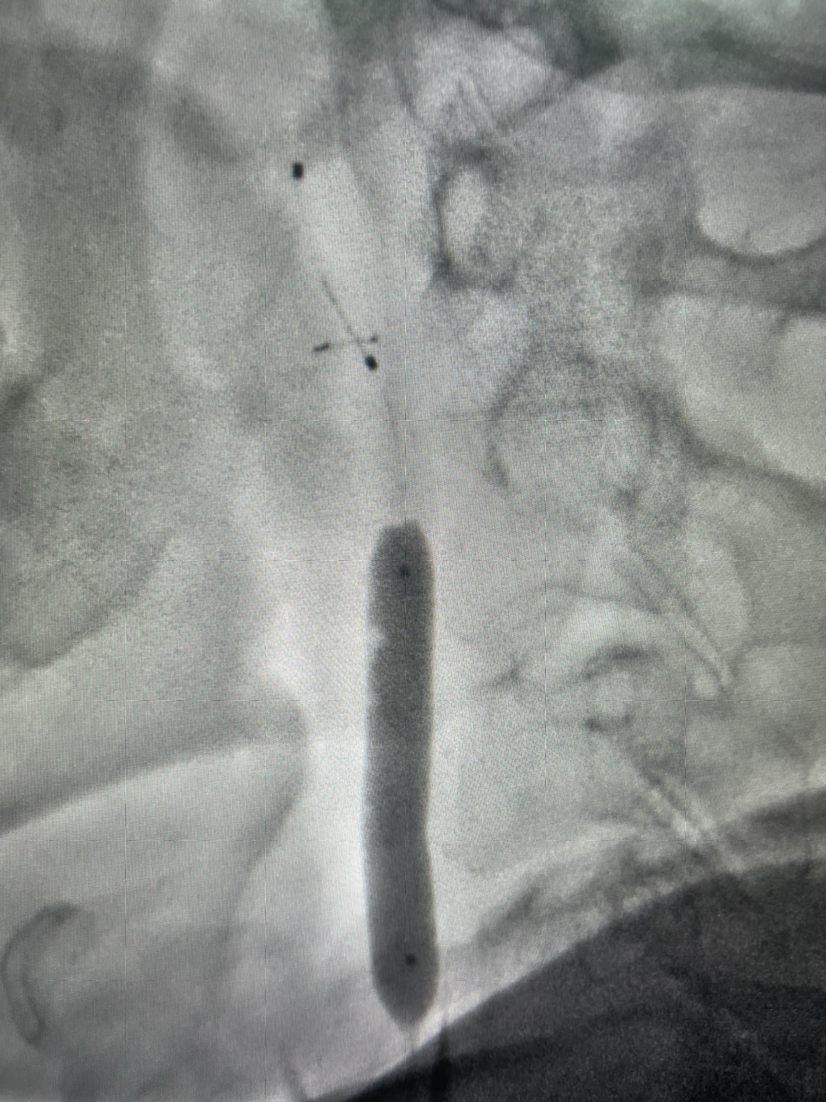

颈动脉支架植入

支架植入后正位

支架植入后侧位